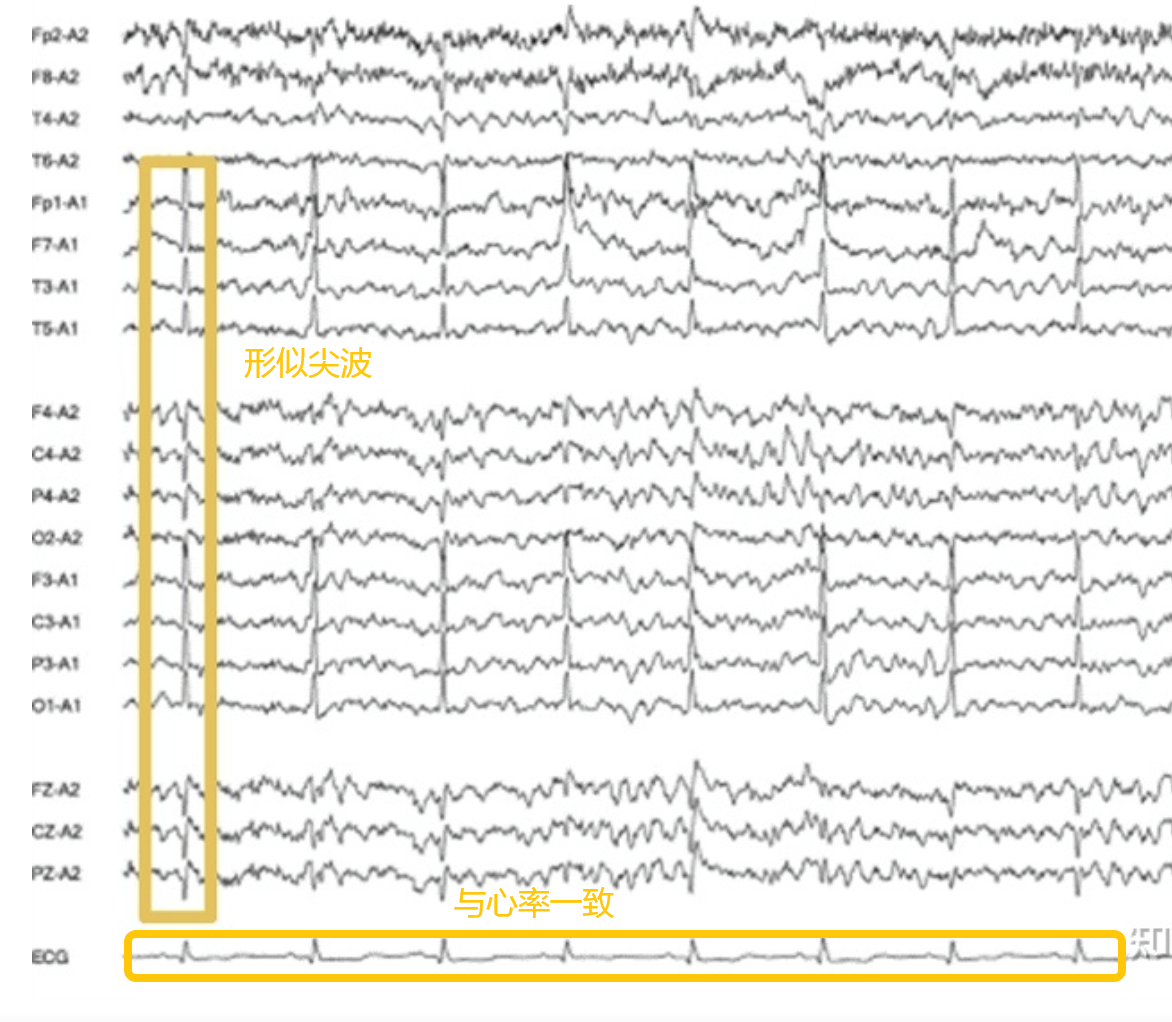

(5)心电伪迹

特征:形似尖波或棘波,频率与心率一致在这里插入图片描述